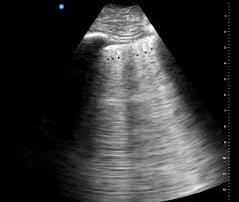

Diagnóstico por ecografía pulmonar

La ecografía pulmonar, también conocida como ultrasonido pulmonar, se ha convertido en una herramienta diagnóstica de creciente relevancia en la medicina moderna. Su capacidad para ofrecer imágenes en tiempo real y de manera no invasiva resulta particularmente útil en la evaluación de una amplia gama de condiciones respiratorias. Comprender las líneas y patrones que se observan en la ecografía ayuda a los profesionales de la […]